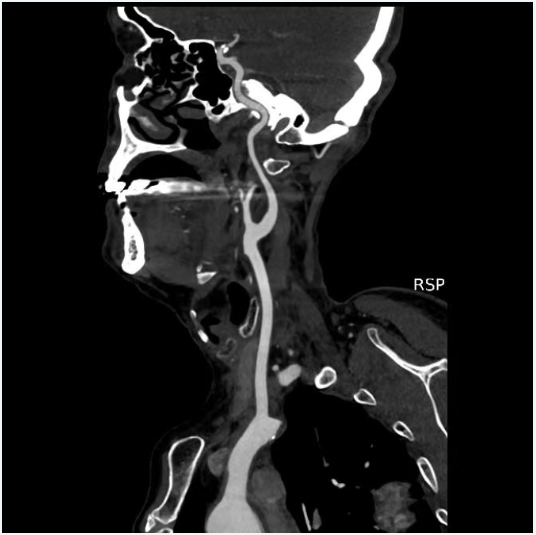

二、術前影像

image.png